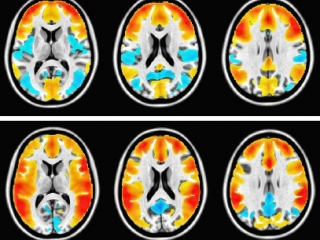

• L'équipe a utilisé la neuroimagerie fonctionnelle pour étudier l'activité cérébrale spontanée de patients adultes dont le premier épisode dépressif s'était produit pendant leur adolescence. Grâce à l'analyse dynamique d'images IRM de l’activité cérébrale spontanée, cette recherche publiée en 2021 dans la revue Biological Psychiatry: Cognitive Neuroscience and Neuroimaging a détecté une inflexibilité dynamique entre le réseau affectif limbique et les réseaux cognitifs préfrontaux. Grâce à des approches mathématiques qui tiennent compte des propriétés statistiques et dynamiques du fonctionnement cérébral, l'équipe a pu caractériser les réseaux fonctionnels intervenant dans la rumination de pensées, pratique humaine purement subjective, fréquente chez les jeunes, mais souvent négligée. Il a été possible de montrer que ces "réseaux des ruminations" sont impliqués dans l'apparition de symptômes "d'internalisation" (symptômes d'anxiété, de dépression) ou "d'externalisation" (impulsivité, agitation, addiction...). L'équipe a ainsi pu conclure que les ruminations sont intéressantes pour des recherches préventives en santé mentale.